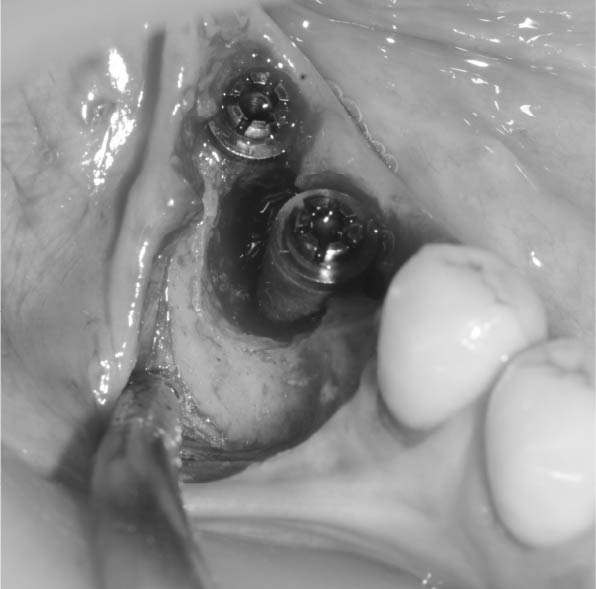

外科手術にて対応することが多い

インプラントの周りを歯茎を切って開いて、徹底的に消毒

骨に置換するカルシウムを主成分とする粉を詰め、膜で覆う

骨の欠損の進行次第ではインプラントを撤去し、骨の治癒を待った後、再度インプラントを埋入する

以上、インプラント周囲炎の治療法を述べましたが、天然の歯の歯周病と比べて難易度は高い。その理由としては、インプラントは骨との結合を良くするために表面をあえて粗造にしてある。インプラント周囲炎に罹患してない時は問題ないが、一度罹患してしまうと骨が溶け、インプラントの粗造な表面が露出するので汚れが溜まりやすく、進行しやすい。